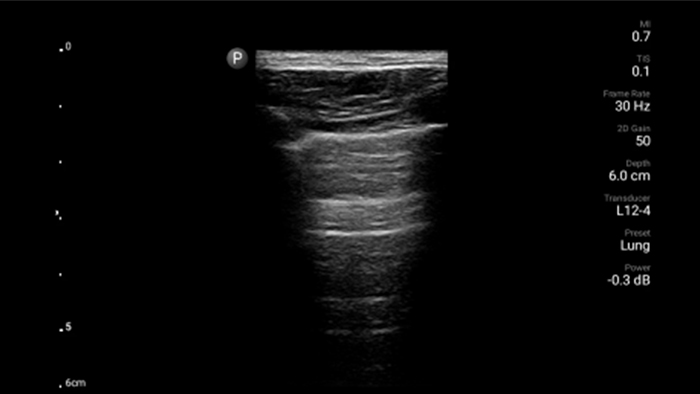

Lumify puede ayudar a obtener resultados similares a los de una tomografía computarizada de tórax al evaluar la neumonía y el síndrome de dificultad respiratoria en adultos.

• Rango extendido de frecuencias de operación entre 12 y 4 MHz • Tamaño de apertura: 34 mm • 2D, Doppler orientable a color, Modalidad M, XRES avanzado e imágenes armónicas multivariables, SonoCT • Imágenes de alta resolución para aplicaciones superficiales: tejidos blandos, vasculares, superficiales, musculoesqueléticos y pulmonares • Marcador de línea central • Transductor USB-C con cable reemplazable